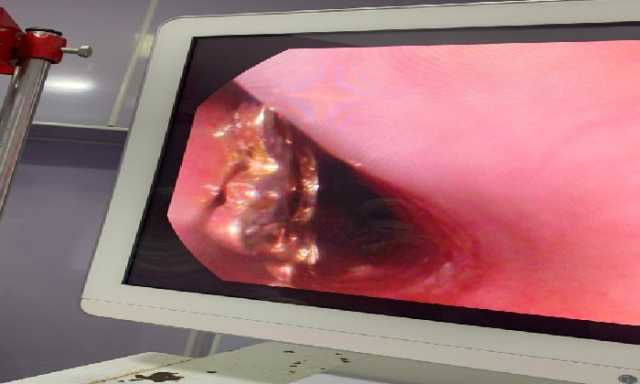

وأوضح وكيل وزارة الصحة أن قسم المناظير بمستشفى أبو كبير شهد نجاح مميز في إنقاذ الطفلة التي تبلغ من العمر ٥ سنوات، وقامت بابتلاع سلسلة معدنية حادة ومدببة وأطرافها قادرة على إحداث جروح أو ثقوب بالزور أو داخل المعدة، وبعد استقبالها مساء أمس الثلاثاء بمستشفى مشتول السوق المركزي، وتم التنسيق السريع من خلال مركز الخدمات الطارئة ١٣٧ بالمديرية، وتحويل الحالة بسيارة الإسعاف إلى مستشفى أبو كبير في وقت قياسي، وتم التدخل العاجل بالمنظار بعد إجراء كافة الفحوصات الطبية اللازمة لها، واستخراج السلسلة من المعدة دون أي مضاعفات، وسط متابعة وتدخل فوري من الفريق الطبي بقيادة الدكتور محمد عصام خلال الفترة المسائية.

وأضاف وكيل وزارة الصحة بالشرقية بأن الفريق الطبي بقسم مناظير الكبد والجهاز الهضمي بالمستشفى، قام أيضاً بإجراء ٩ مناظير قولونية ومناظير معدة تشخيصية وعلاجية، منهم منظار لمريضة تعاني من قيء دموي حاد نتيجة نزيف من دوالي المعدة وتم حقنها بالمنظار العلاجي، كما تم استئصال زوائد لحمية متعددة بالقولون لمريض آخر يعاني من نزيف شرجي مستمر، هذا بالإضافة إلى إجراء منظار قولوني لطفل يبلغ من العمر ٤ سنوات يعاني من إمساك مزمن ونزيف شرجي، وتم أخذ عينات من قرح وزوائد بالأمعاء الدقيقة لتحليل الأنسجة.